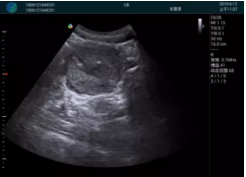

病例一:

清晰顯示孕囊,通過軟件包計算孕齡7w+6d

M20實(shí)時引導(dǎo),術(shù)中清晰顯示孕囊被破壞和抽吸針的過程,清晰顯示吸引針

抽吸結(jié)束后縱切子宮,孕囊已被完全抽吸,未見明顯殘留

橫切子宮,發(fā)現(xiàn)右側(cè)宮腔靠近宮角處有少許脫模樣殘留

M20引導(dǎo)下,抽吸針找到右側(cè)宮角處再次清掃

二次抽吸后再次進(jìn)行超聲檢查,宮腔未見殘留,宮腔線清晰顯示

超聲引導(dǎo)下可視化人流是技術(shù)安全性的保障,一般對人流術(shù)設(shè)備預(yù)算不高,M20具備婦產(chǎn)科軟件包,且穿透力圖像質(zhì)量好,既滿足人流引導(dǎo)需要,也可用于床旁超聲的需求。